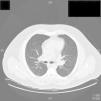

En la radiografía de tórax se halló una masa parahiliar que se correlacionó con múltiples adenopatías mediastínicas, parahiliares y supraclaviculares, así como múltiples nódulos pulmonares en la TAC de alta resolución (fig. 1). Ante la sospecha de un proceso linfoproliferativo se realizó una mediastinoscopia para la toma de una biopsia ganglionar. En la histología se evidenció una inflamación crónica granulomatosa no caseificante con tinción de Ziehl-Nielsen negativa y PCR para Mycobacterium tuberculosis negativa (fig. 2).

Transcurridos 6 meses desde el diagnóstico de sarcoidosis y en ausencia de tratamiento con anti-TNF, se constató una mejoría radiológica (fig. 3) con disminución notable de las linfadenopatías y hemograma dentro de la normalidad.